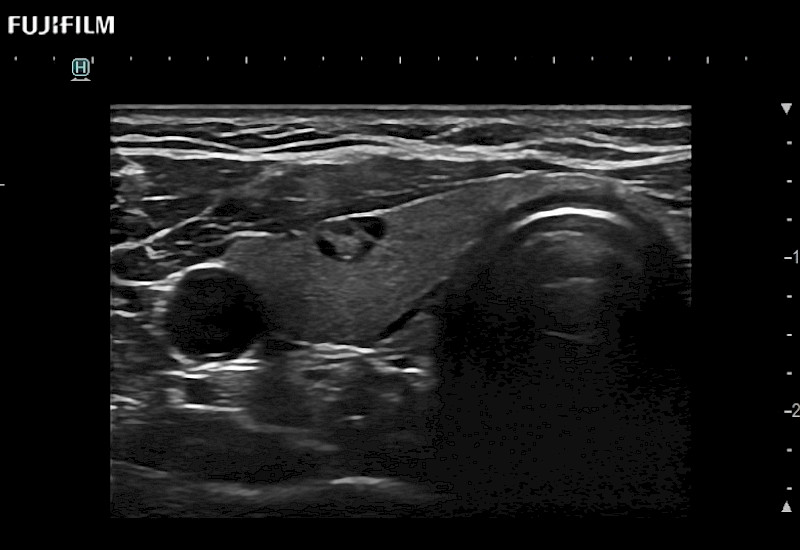

Curved array deep penetration “T” style finger-grip transducer for open surgical procedures.